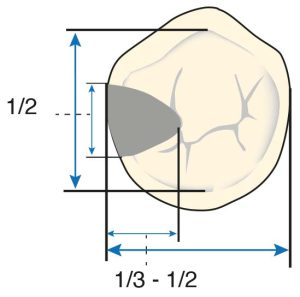

The occlusal rest seat is triangular with the base at the marginal edge and the apex at the center of the tooth. The outer edges of the rest seat and especially the apex of the triangle should be rounded. The ideal width for the occlusal rest seat is approximately half the distance between the buccal and lingual cusp tips for premolars and slightly less for molars (Figure 10-31).